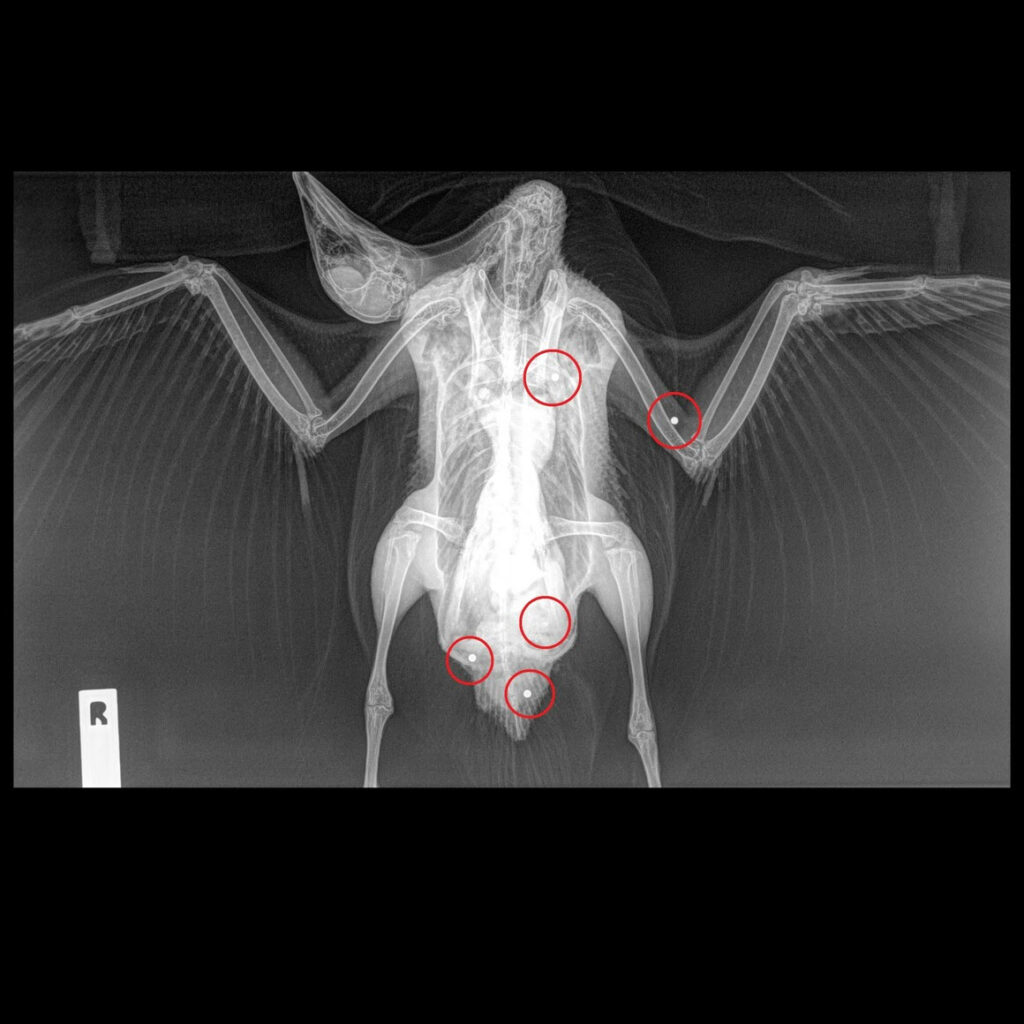

Rescuers continued searching for wounded birds after the season closed. This wounded Wood Duck (below) was found on Lake Wooroonook five days after the season ended. X-rays revealed five pellets in the bird’s body so the vet decided the most humane option was euthanasia. See Yahoo News article here.

This bird epitomises the suffering wounded birds endure during – and after – recreational duck shooting seasons.